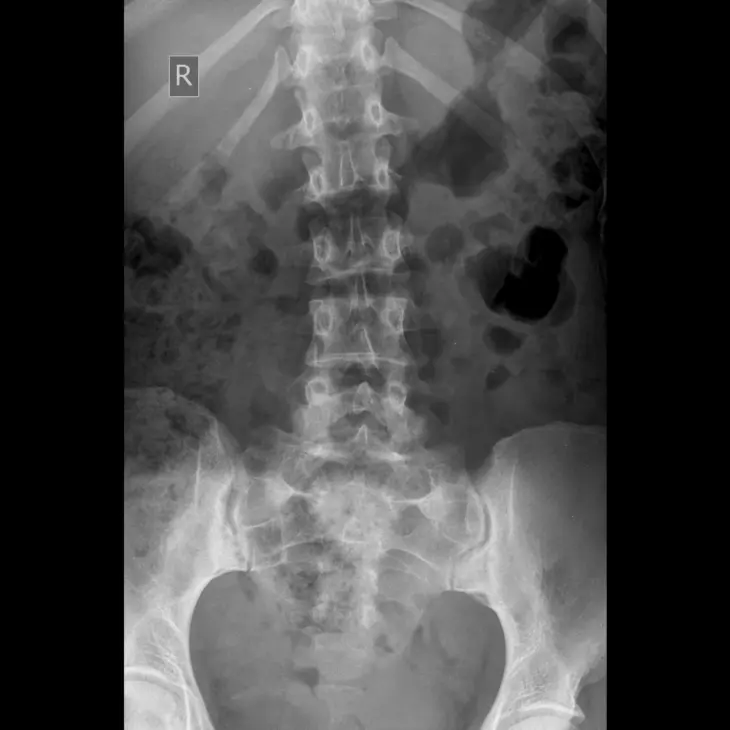

O diagnóstico começa com avaliação clínica detalhada e exames de imagem. Radiografias da coluna identificam a fratura vertebral por compressão e a ressonância magnética confirma se a fratura é recente (aguda) e se há edema ósseo, o que indica que a vertebroplastia pode ser eficaz. Exames laboratoriais e avaliação da densidade óssea complementam a investigação.

A vertebroplastia percutânea é um procedimento minimamente invasivo utilizado para tratar fraturas vertebrais por compressão. Essas fraturas são comuns em pacientes com osteoporose, tumores ósseos ou metástases na coluna e causam dor intensa nas costas que limita a movimentação e compromete a qualidade de vida.

A vertebroplastia percutânea é realizada em centro cirúrgico, sob anestesia local com sedação ou anestesia geral. O paciente fica posicionado de bruços e, com auxílio de fluoroscopia (raio-X em tempo real), o cirurgião insere uma agulha especial pela pele até o corpo vertebral fraturado. Através dessa agulha, o cimento ósseo é injetado de forma controlada, preenchendo a fratura e estabilizando a vértebra. O procedimento dura em média 30 a 60 minutos por vértebra tratada.